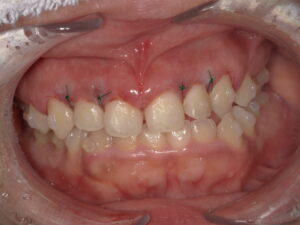

以下の症例は、当院で、インビザライン矯正と、歯冠長延長術を行った症例です。

局所麻酔を打ってから縫合まで20分位の処置です。

術直後

術後 (矯正は、治療中です)

患者さんから、写真使用の許可を得ています。